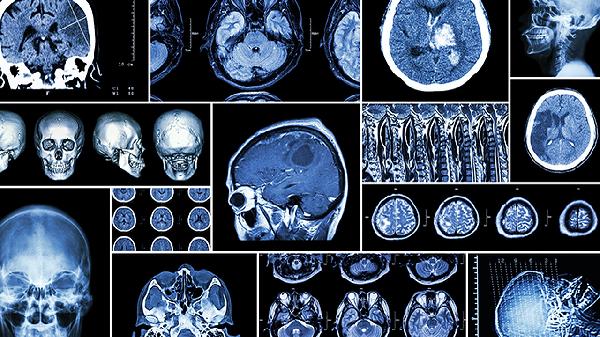

脑血栓怎么治才能有效消除

脑血栓的治疗方式包括溶栓、抗凝、抗血小板、手术以及康复等多种方法。这种疾病通常与动脉硬化、高血压、糖尿病、心房颤动及血液黏稠度高有关。